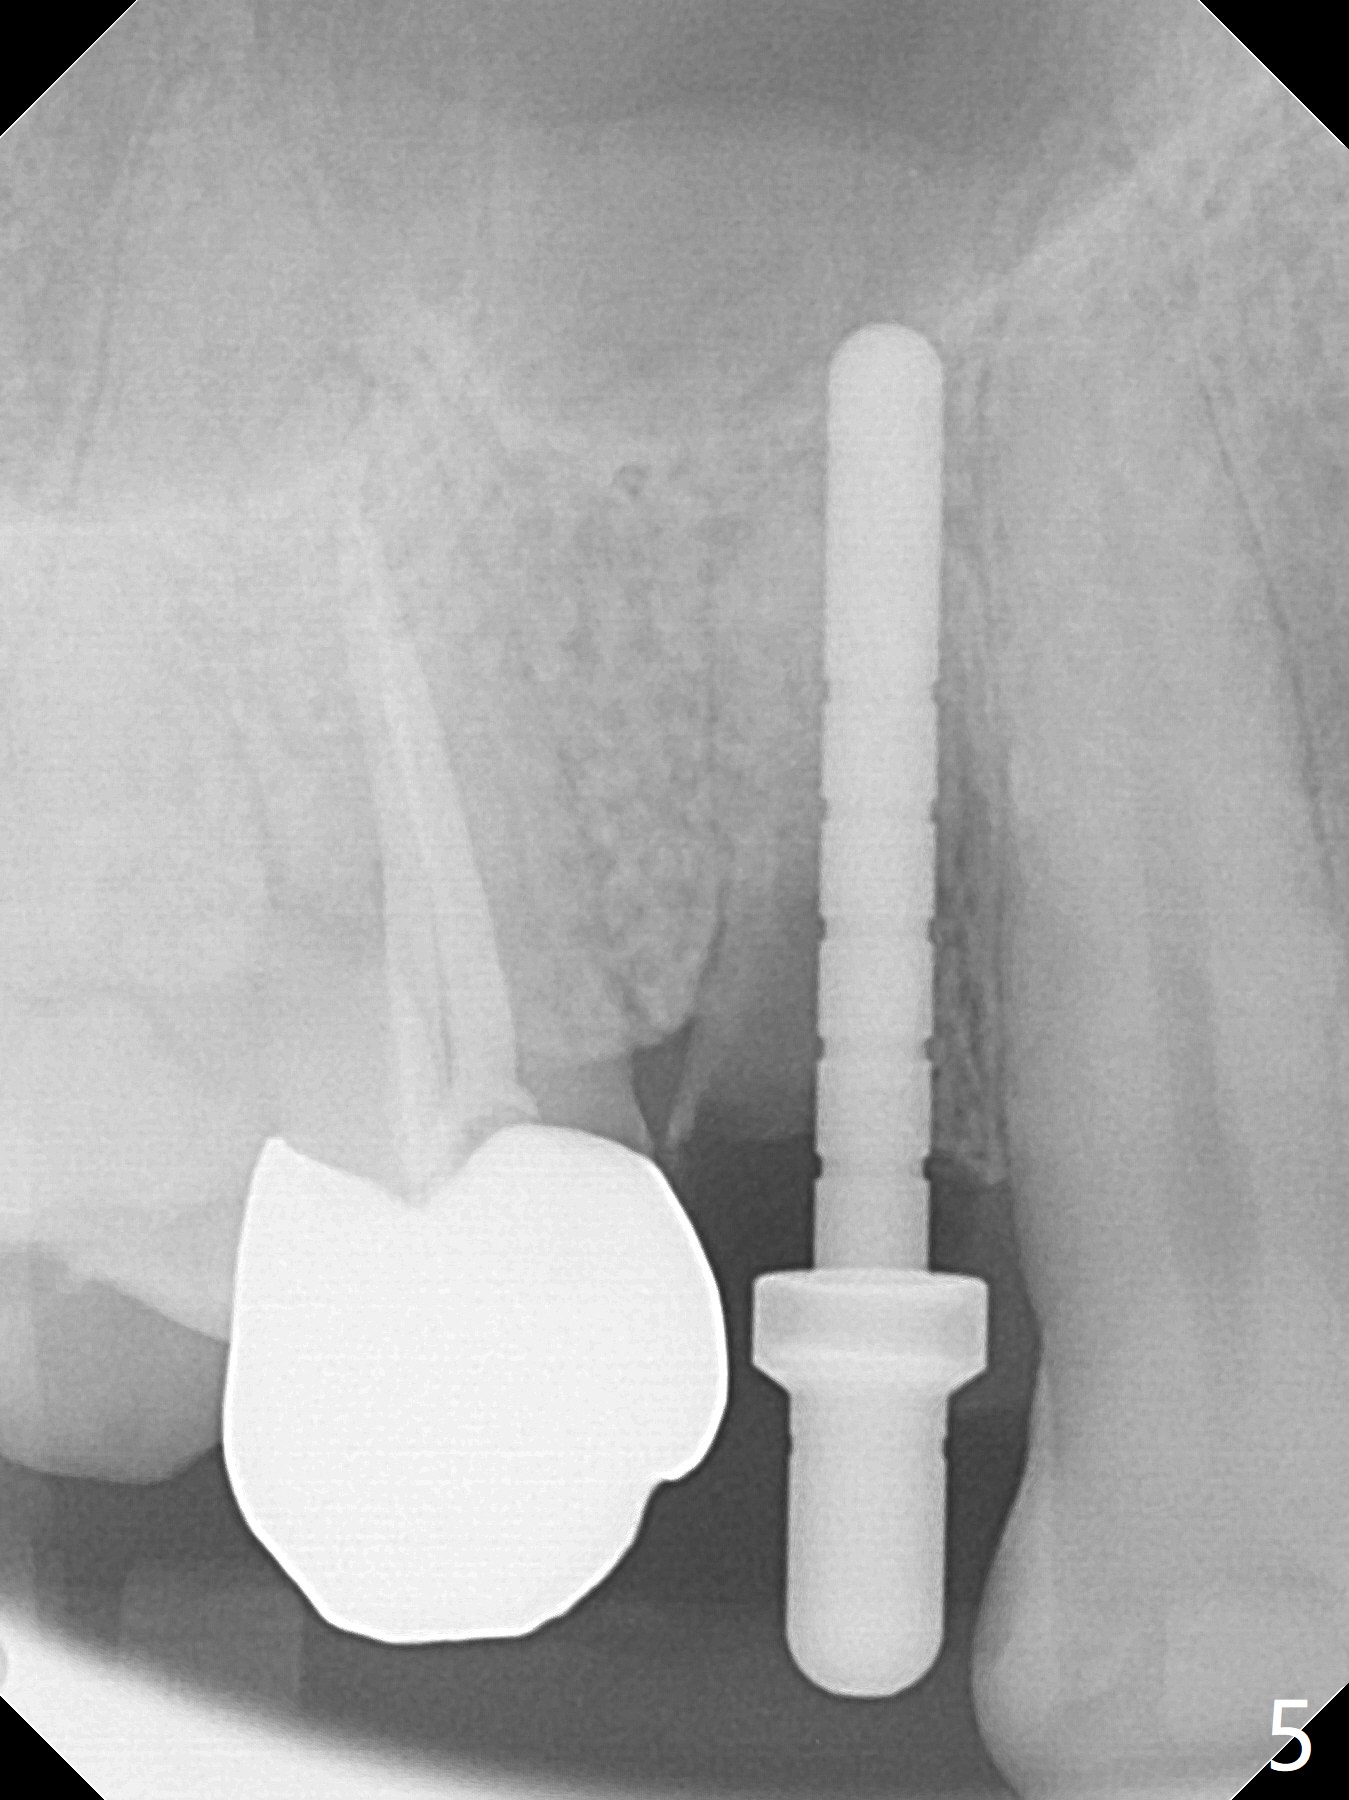

The buccal plate is normal at the tooth #5 (Fig.1) with the loose palatal fragment (Fig.2 P). Extraction leads to root fracture. Sectioning removes the palatal portion of the root and keeps the buccal semilunar piece (Fig.3 *); the mesiopalatal plate is resorbed (P). Initial osteotomy is off (Fig.4 (R: remaining root)). Redirection improves the trajectory (Fig.5). With the 2nd redirection (Fig.6 (4.5 mm tap)), a 4.5x12 mm implant is placed with 50 Ncm and sinus lift (Fig.7 black *); bone graft is placed with emphasis on the palatal defect (white *). As usual, an immediate provisional is fabricated. In fact the abutment may be not completely seated because of contact with the mesial crest. Prepare anesthetic and 5.5 mm profile drill. Take parallel BW or PA. Take occlusal photos to show no buccal or mesiopalatal atrophy. After 5.5 mm profile drill 11 months postop, the abutment has no contact with the mesial crest (Fig.8 <). Since the proximal contact between #3 and 4 is light with food impaction, the provisional at #5 is fabricated with tight distal contact. When the patient returns for final crown cementation (Fig.9), the food impaction is minimal between #3 and 4. The distal black triangle (Fig.10 *) and exposure of the abutment margin (^) are partially related to provisional fabrication and should dissolve over time considering socket shield.